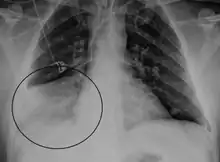

.png)

The identification of HMPV has predominantly relied on reverse-transcriptase polymerase chain reaction (RT-PCR) technology to amplify directly from RNA extracted from respiratory specimens. Alternative more cost-effective approaches to the detection of HMPV by nucleic acid-based approaches have been employed and these include:

- detection of hMPV antigens in nasopharyngeal secretions by immunofluorescent-antibody test

- the use of immunofluorescence staining with monoclonal antibodies to detect HMPV in nasopharyngeal secretions and shell vial cultures

- immunofluorescence assays for detection of hMPV-specific antibodies

- the use of polyclonal antibodies and direct isolation in cultured cells.